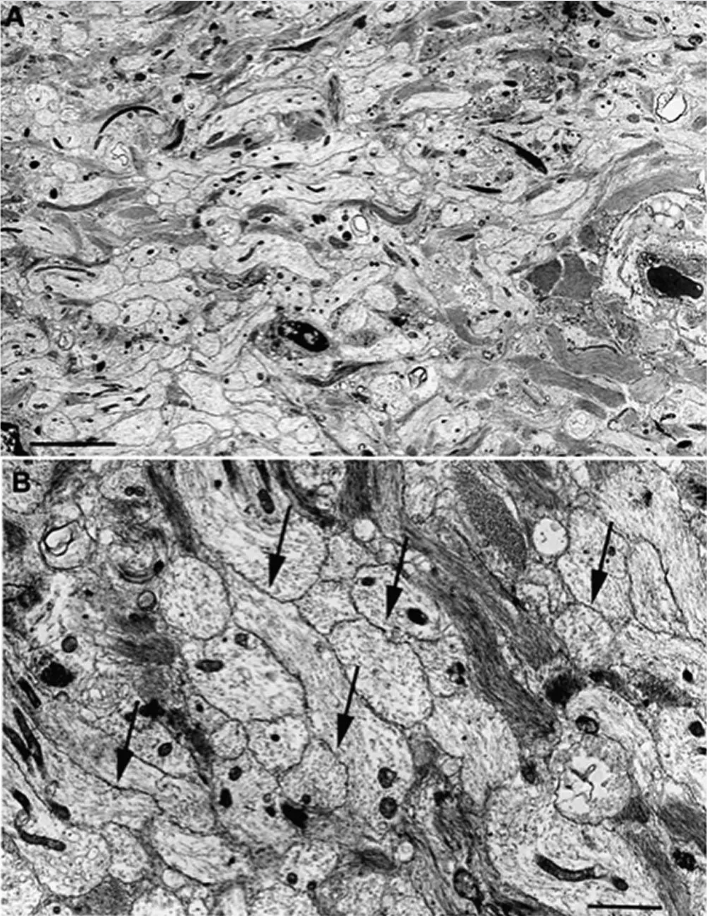

图a,电子显微照片显示多发性硬化症患者神经根慢性脱髓鞘(比例尺10μm

再生的轴突开始髓鞘化臂丛损伤的患者常经过段时间后可恢复部分神经

后10周不同组别组织学染色图片及透射电镜图片,用于观察髓鞘再生情况